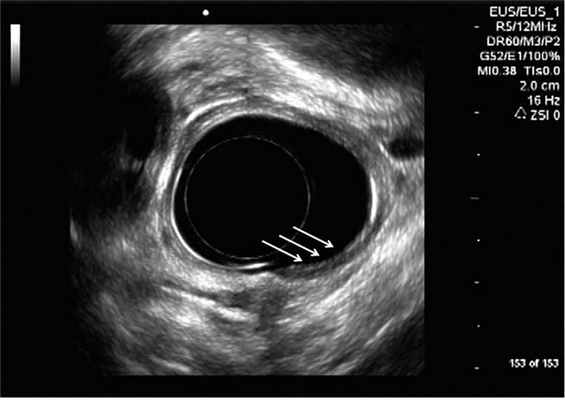

Больной Ч., 61 года, находился на стационарном лечении по поводу ишемической болезни сердца в Институте хирургии им. А.В. Вишневского в 2011 г. По принятому в клинике протоколу предоперационного обследования больному выполнена эзофагогастродуоденоскопия, при которой в пищеводе на расстоянии около 25 см от резцов визуализировано подслизистое образование (липома?) округлой формы диаметром 0,7-0,8 см; слизистая над ним гладкая, белесоватая, плотная (рис. 1, а, стрелка 1). Рисунок 1. Данные обследования 2011 г. а - эндофотограмма: подслизистое новообразование (стрелка 1) и полная эрозия слизистой пищевода (стрелка 2). Рисунок 1. Данные обследования 2011 г. б - эндосонограмма. Подслизистое новообразование пищевода (стрелкой указан второй эхослой). Также в пищеводе на расстоянии 27 см от резцов отмечается участок приподнятой слизистой овальной формы размером 0,7×0,5 см (полная эрозия?) (рис. 1, а, стрелка 2). Выполнена щипковая биопсия из описанного участка слизистой, в полученном материале фрагменты многослойного эпителия с дистрофическими и воспалительными изменениями. Учитывая наличие подслизистого новообразования и подозрительного участка слизистой в средней трети пищевода, больному выполнили эндосонографию пищевода: визуализировано образование наибольшим размером 7,2 мм, по структуре гипоэхогенное, с четким, ровным, гиперэхогенным контуром, исходящее из мышечной пластинки слизистой оболочки стенки пищевода (2-й эхослой). Предполагали наличие лейомиомы или липомы. При сканировании участка измененной слизистой отмечается некоторое утолщение слизистой оболочки и ее мышечной пластинки, слоистое строение пищевода в данной зоне не нарушено (рис. 2, а). Рисунок 2. Данные обследования 2012 г. а - эндофотограмма: ранний рак пищевода (окраска раствором Люголя). Больной был успешно оперирован по поводу основного заболевания и выписан с рекомендацией выполнения динамической ЭГДС через 1 год.

Больной повторно госпитализирован в Институт хирургии им. А.В. Вишневского для дообследования и решения вопроса о дальнейшей тактике лечения. Выполнена КТ грудной и брюшной полости, по результатам которой на уровне средней трети пищевода имеется неравномерное утолщение стенки на протяжении 25 мм с наличием фрагментарного сужения просвета. Расстояние от начального сужения до диафрагмы 13 см. Участков избирательного накопления контрастного вещества в стенке не определяется. Параэзофагеальные лимфатические узлы не увеличены. Следующим этапом была выполнена ЭГДС, щипковая биопсия со срочным цитологическим исследованием, эндосонография. При заборе материала вновь было отмечено кровотечение, которое остановлено эндоскопически с применением аргоноплазменной коагуляции. Результаты эндосонографии: в стенке пищевода на расстоянии 25 см от резцов визуализируется подслизистое образование наибольшим диаметром 7,2 мм, образование по структуре гипоэхогенное, имеет четкий, ровный, гиперэхогенный по структуре контур. Данное образование исходит из мышечной пластинки слизистой оболочки стенки пищевода (второй эхослой). На расстоянии около 27 см от резцов визуализировано гипоэхогенное образование, захватывающее 1 / 3 окружности пищевода на протяжении около 1 см, частично прорастающее подслизистый слой, мышечный слой прослеживается на всем протяжении (рис. 2, б). Рисунок 2. Данные обследования 2012 г. б - эндосонограмма: ранний рак пищевода. Область поражения слизистой пищевода указана стрелками. Визуализируется увеличенный параэзофагеальный лимфатический узел диаметром до 6 мм, овальной формы, гипоэхогенного строения. Результаты срочного цитологического исследования: плоскоклеточный рак.

Эндосонография является «золотым стандартом» диагностики эпителиальных и подслизистых образований пищевода. Достоверность метода при стадировании опухоли пищевода по критериям T и N достигает 80 и 77% соответственно [4] и около 95% при определении интрамуральных опухолей или экстраорганного сдавления пищевода патологическими структурами или соседними органами, при дифференцировке происхождения подслизистых новообразований [1].